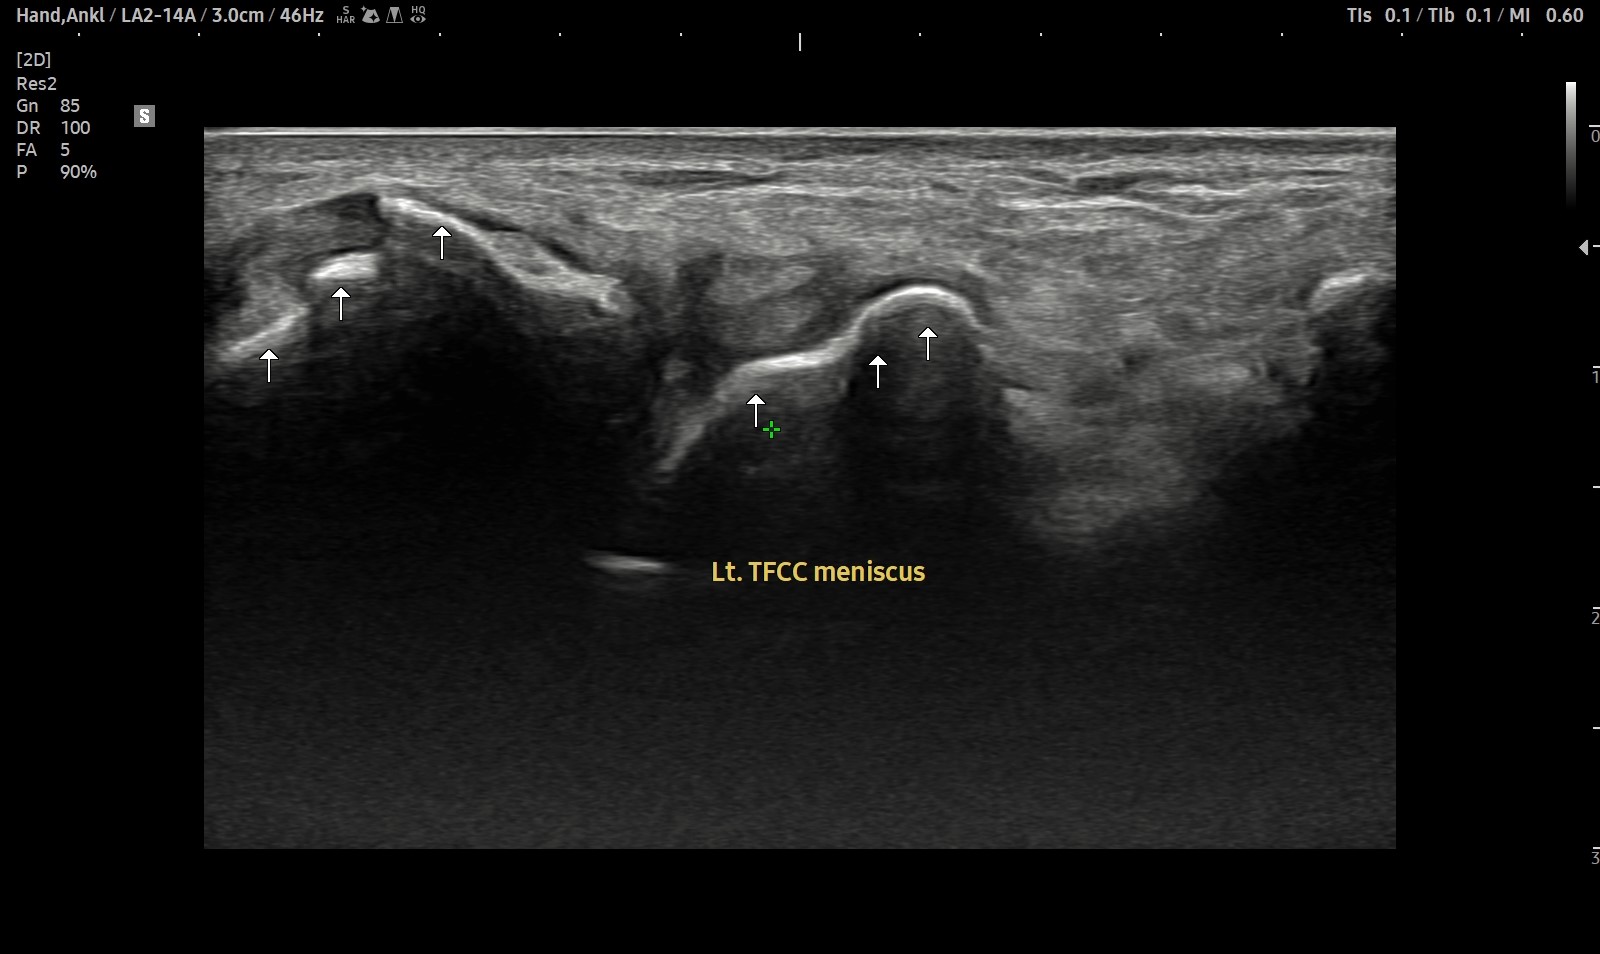

- 치료기간 : 2025 . 2 . 22 ~ 2025. 9 . 20

- 치료횟수 : 4cycle (20회)

8cycle 계획에서 빠른 호전으로 조기 치료 종결 case.

치료 전

치료 후